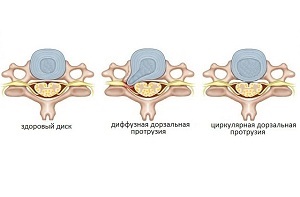

Dorsalis formája a degeneratív folyamat két csoportba sorolhatjuk:

- diffúz. A patológiai folyamatot jellemzi ismételt, nem egyenletes kiemelkedés, amely felgyorsítja a kialakulása egy porckorongsérv, a tömege más szövődmények;

- kör alakú. Ez eltér a korábbi formájában a tény, hogy a kiemelkedés a bevétel egyenletesen, ellentétben a fent leírt kiálló a gerinc. A patológia vezet éles fájdalomérzet, amelyeket nehéz kezelni.